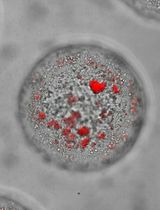

In this protocol, we take the prostate cancer cell line PC-3 as an example, describe the hands-on procedures of cell preparation, intratibial injection, monitoring tibial tumor growth, and post tissue collection analyses, highlight the critical steps in cell preparation and intratibial injection, and detail how to quantitatively analyze the tibial tumors in histological samples.